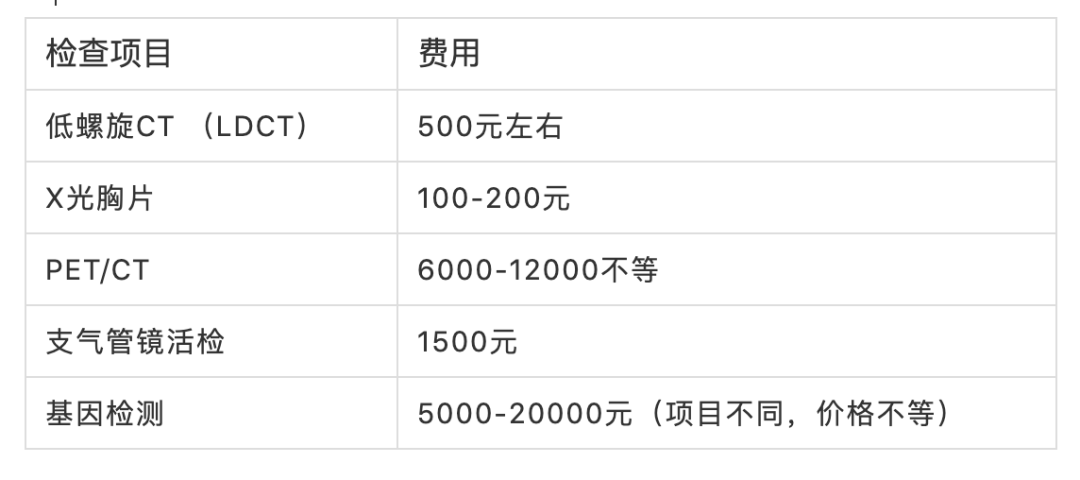

肺癌的治疗费用

肺癌的治疗费用